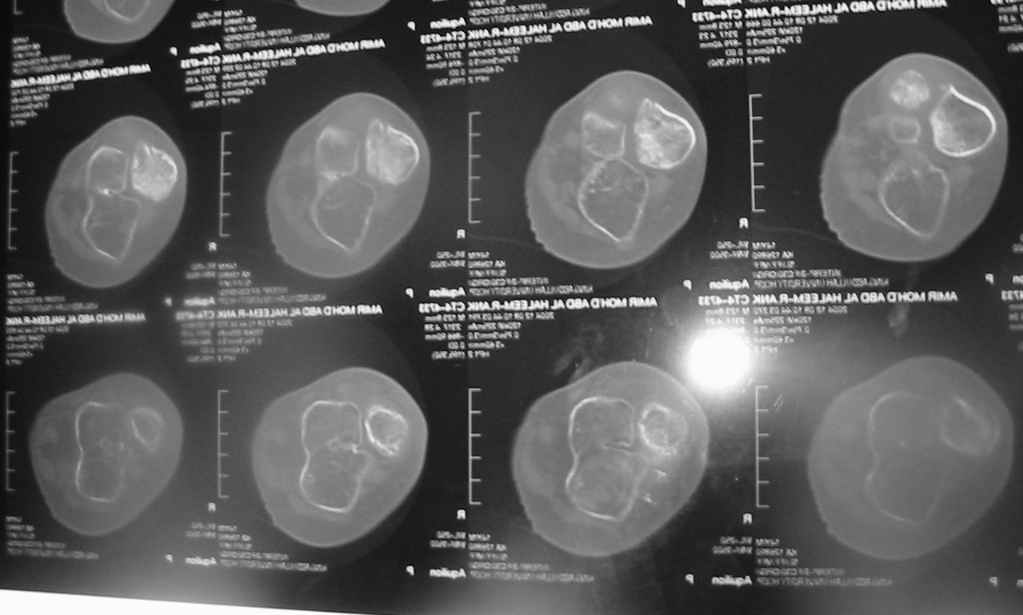

Судя по представленным фото и Рг граммам, у 13 летнего ребенка врождённая гемимелия большеберцовой кости, таранно-пяточный синостоз Из-за отставания в росте большеберцовой кости (остутствует дистальный эпифиз с зоной роста) произошла компенсаторная гиперофия малоберцовой кости, на которую приходится основная нагрузка (спонтанная тибиализация малоберцовой кости). Как результат дисбаланса осевого роста вторично возникла эквино-варусная деформация стопы. Продолжающийся рост ребёнка (до естественного закрытия зон роста) будет приводить к усугублению деформации по приведенным выше причинам.

Поднадкостничную остеотомию большеберцовой кости в средней трети с формированием синостоза с малоберцовой ( активно растущей) костью и второй уровень в области дистального тиб/фиб синдесмоза- достигается баланс роста( средне-медиальный и латеральный отделы) в области измененного голеностопного сустава. Коррекция эквино-варусной деформации стопы в аппарате после чрезкожной сегментарной тенотомии ахилова сухожилия. Дело

кропотливое и длительное.